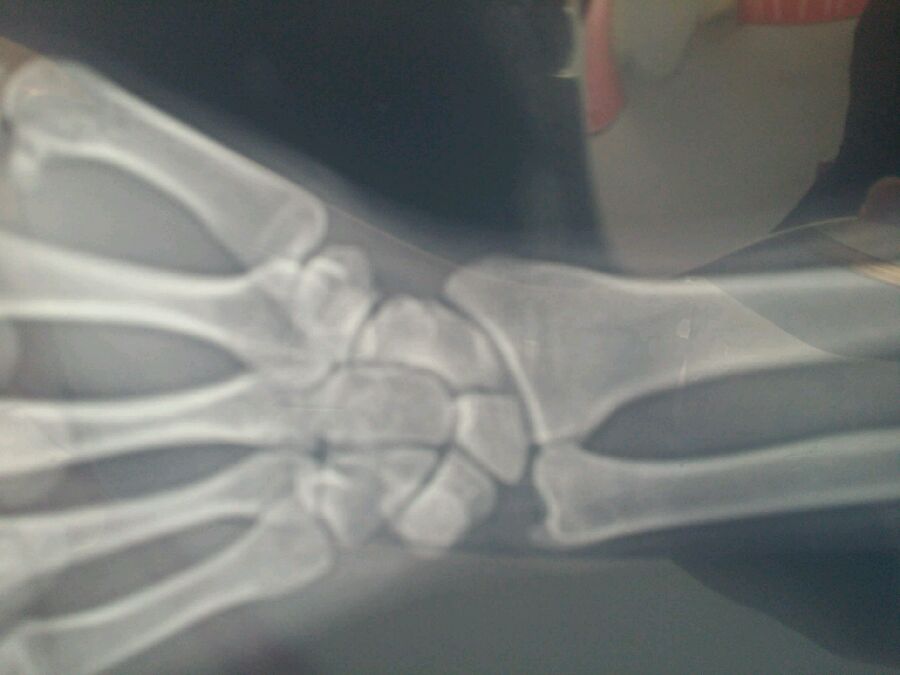

骨裂喽

粉末性骨折

桡骨

是不是手舟骨???用绷带蹦蹦也行